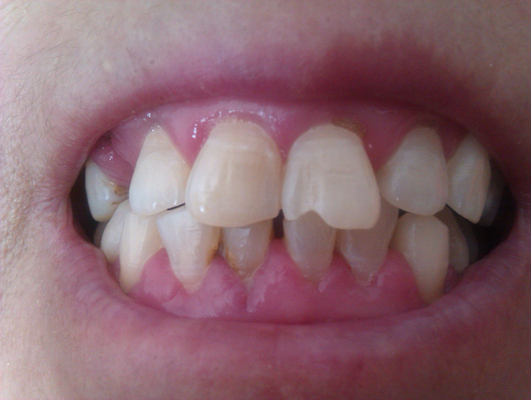

牙齦炎圖片

牙齦炎和牙周炎